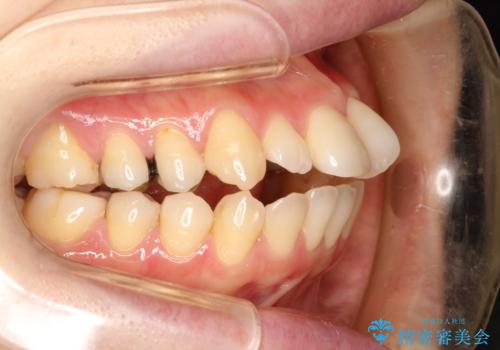

矯正後の後戻りで前歯にガタツキができてしまった インビザラインで改善

- 子どものときにワイヤー矯正をしていたが、後戻りによって前歯のガタツキが気になってきたとのことで来院されました。

アライナー矯正希望だったため、インビザラインによる治療を行いました。

- 7ヶ月